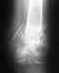

Здравствуйте, 20 октября этого года на катке упала на прямую руку,увезли на скорой в травмпункт (это было не в нашем городе) боли были ужасные, сдедали рентген http://s40.radikal.ru/i088/1211/85/1610fd4d96cb.jpg и http://s47.radikal.ru/i118/1211/3c/2d6b65e9faee.jpg . Сказали что у меня осколочный перелом шейки плеча -удачный перелом наложили гипс по типу дезо. Приехав к себе погшла на прием к травмотологу он сказал ходить месяц в гипсе.16 читсла прийти на рентген. 16 ноября , пройдя рентген врач сказал что у меня очень медленно срастаеться кость.(хотя Я активно пью мумие и кальций, ем холодец и молочные продукты).После он сказал что нужно всетаки сделать ренген под другой проекцией тк итог снимка - http://s51.radikal.ru/i133/1211/a1/17289eb441a8.jpg и http://s41.radikal.ru/i094/1211/f5/daf04e875619.jpg . После чего он сказал что у меня всетаки осколочный перелом со смещением, и что нужно делать операцию и ставить пластинку. Прийдя же на очную консультацию с заведующим отделением травмотологии больницы посмотрев все снимки меня опять отправили на рентген http://s019.radikal.ru/i626/1211/7b/1170eb9da07b.jpg и уверили что операция не нужна что у меня статистика отличная и все само зарастет мазоли появились. гипс поменяли поставили по типа картера .Через дня 3 боль была ужасная я не могла ни спать ни сидеть.прийдя обратно к врачам они сказали что гипс "висел"на руке на переломе, поставили между рукой и телом подушечку, те рука стала отведенная, боль исчезло и дискамфорт тоже.Но настараживаетто что уже прошло 2 месяца а осколок нащупываеться рукойи до бугорка ямочка но не большая .и рука в твердая в месте перелома , будто кость под кожей, сказали гематома, но разве она так долго длится 2 месяца.рука иногда сильно ноет